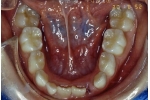

| 初診時